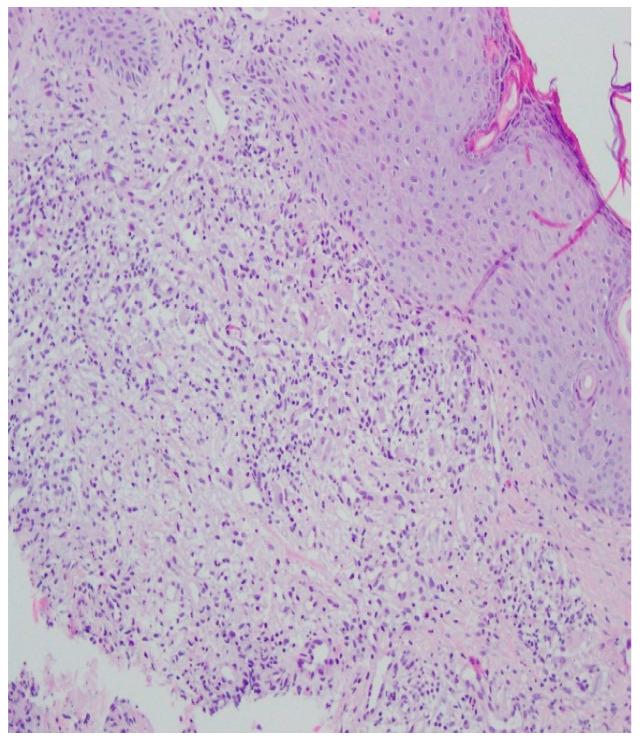

三期梅毒诊断难点:病例报告并文献复习

Challenges in the Diagnosis of Tertiary Syphilis: Case Report with Literature Review.

Tertiary syphilis is a large diagnostic challenge. It is rarely the case that it affects the skin, bone tissue and the eyes at the same time. The presented case shows that extensive symptomatology of syphilis poses a challenge in making a proper diagnosis in patients whose history does not suspect STDs. The study aims to present the case of a young woman hospitalized with a suspected autoimmune disease, diagnosed with symptomatic late syphilis with involvement of the skin, bones and eyes.

摘要

三期梅毒是一个重大的诊断挑战。它很少同时影响皮肤、骨骼组织和眼睛。所呈现的病例表明,在那些病史不怀疑性传播疾病的患者中,广泛的梅毒症状表现给正确诊断带来了挑战。本研究旨在介绍一例年轻女性住院的病例,该女性被怀疑患有自身免疫性疾病,后被诊断为症状性晚期梅毒,涉及皮肤、骨骼和眼睛。